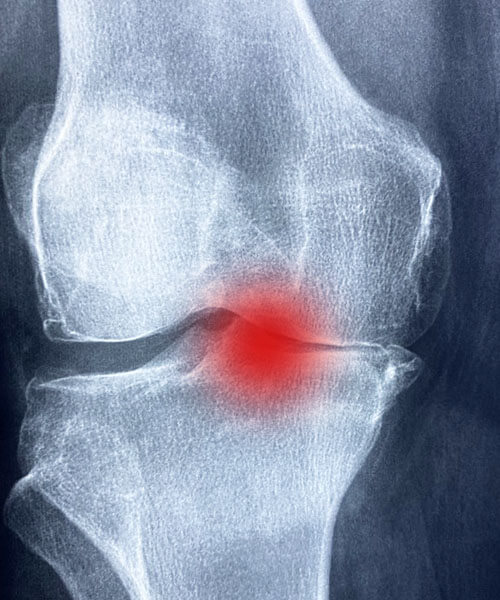

무릎 구부릴 때 통증 의심되는 질환

1. 무릎연골손상 / 무릎인대손상

연골은 무릎의 움직임을 원활하게 해 주고

무릎에 가해지는 충격을 완화시키는

역학을 하는데 이러한 연골이 무릎의

인대와 함께 손상되는 상태를 말합니다.

연골이 손상되면 회복이 잘 되지 않는데

이러한 상태로 오래도록 방치하면

퇴행성관절염으로 이어지기도 합니다.